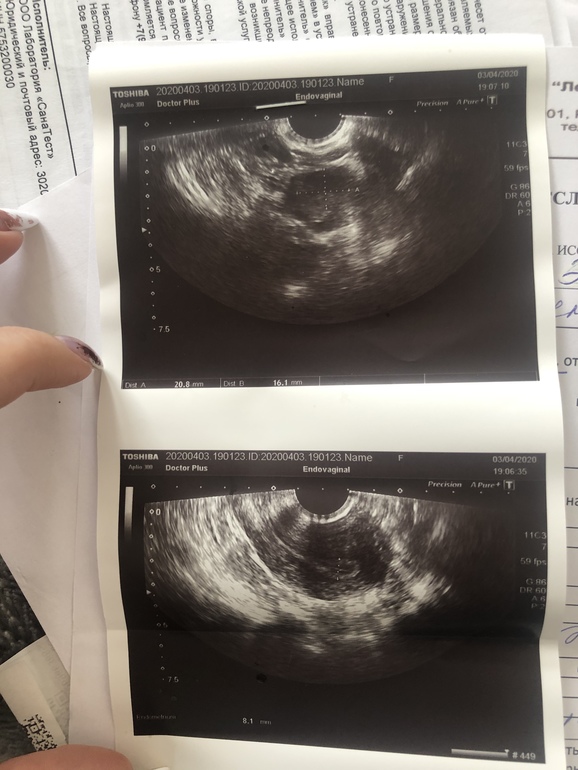

Замершая беременностьтвуйте. Подскажите, пожалуйста. Было 2 беременности подтверждённые лишь по тестам и хгч. Так как не узи не успевала сходить, начинались месячные. Чистки не было. Все выходило само. Месячные начинались на 10-11 день задержки в обоих случаях. Ставят диагноз - привычное невынашивание. Сейчас назначили - дивигель, утрожестан, курантил и акиовегин. Результаты узи и анализов прикрепляю. Подскажите, возможно ли беременность нормальная при таких показателях? Фото узи и гормонов прикрепляю

Узи заключение не разобрать что написано(

Сказали ,что из за тонкого эндометрия ( тогда он был 5,6) и плохого кровотока